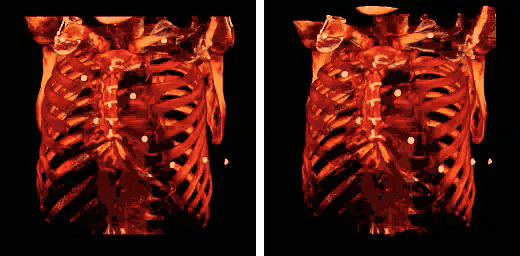

Caja torácica humana - TC (proyección paralela [izquierda] y proyección en perspectiva [derecha]) -

Simulación 3D de la caja torácica -